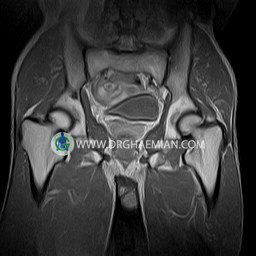

پزشکان اغلب از تصویربرداری ام آر آی برای تشخیص و درمان عارضه های پزشکی که فقط با استفاده از اشعه ایکس یا میدان مغناطیسی و امواج رادیویی قابل مشاهده است، استفاده می کنند. دستگاه ام آر آی تصاویر دقیق از ساختار های داخلی بدن ایجاد می کند. در این کیس استئومیلیت لگن، آتروز و سنیویت دیده می شود.

Technique : coronal STIR , coronal T2 , Axial T1 , axial T2 .

– Heterogeneous signal change (high T2/STIR , low T1) in proximal metaepiphysis of left femur without articular surface irregularity suggestive for bone bruise (stress fracture?), osteomyelitis & arthritis and marrow infiltration (less probable)

– Left hip joint effusion suggestive for synovitis

are seen.